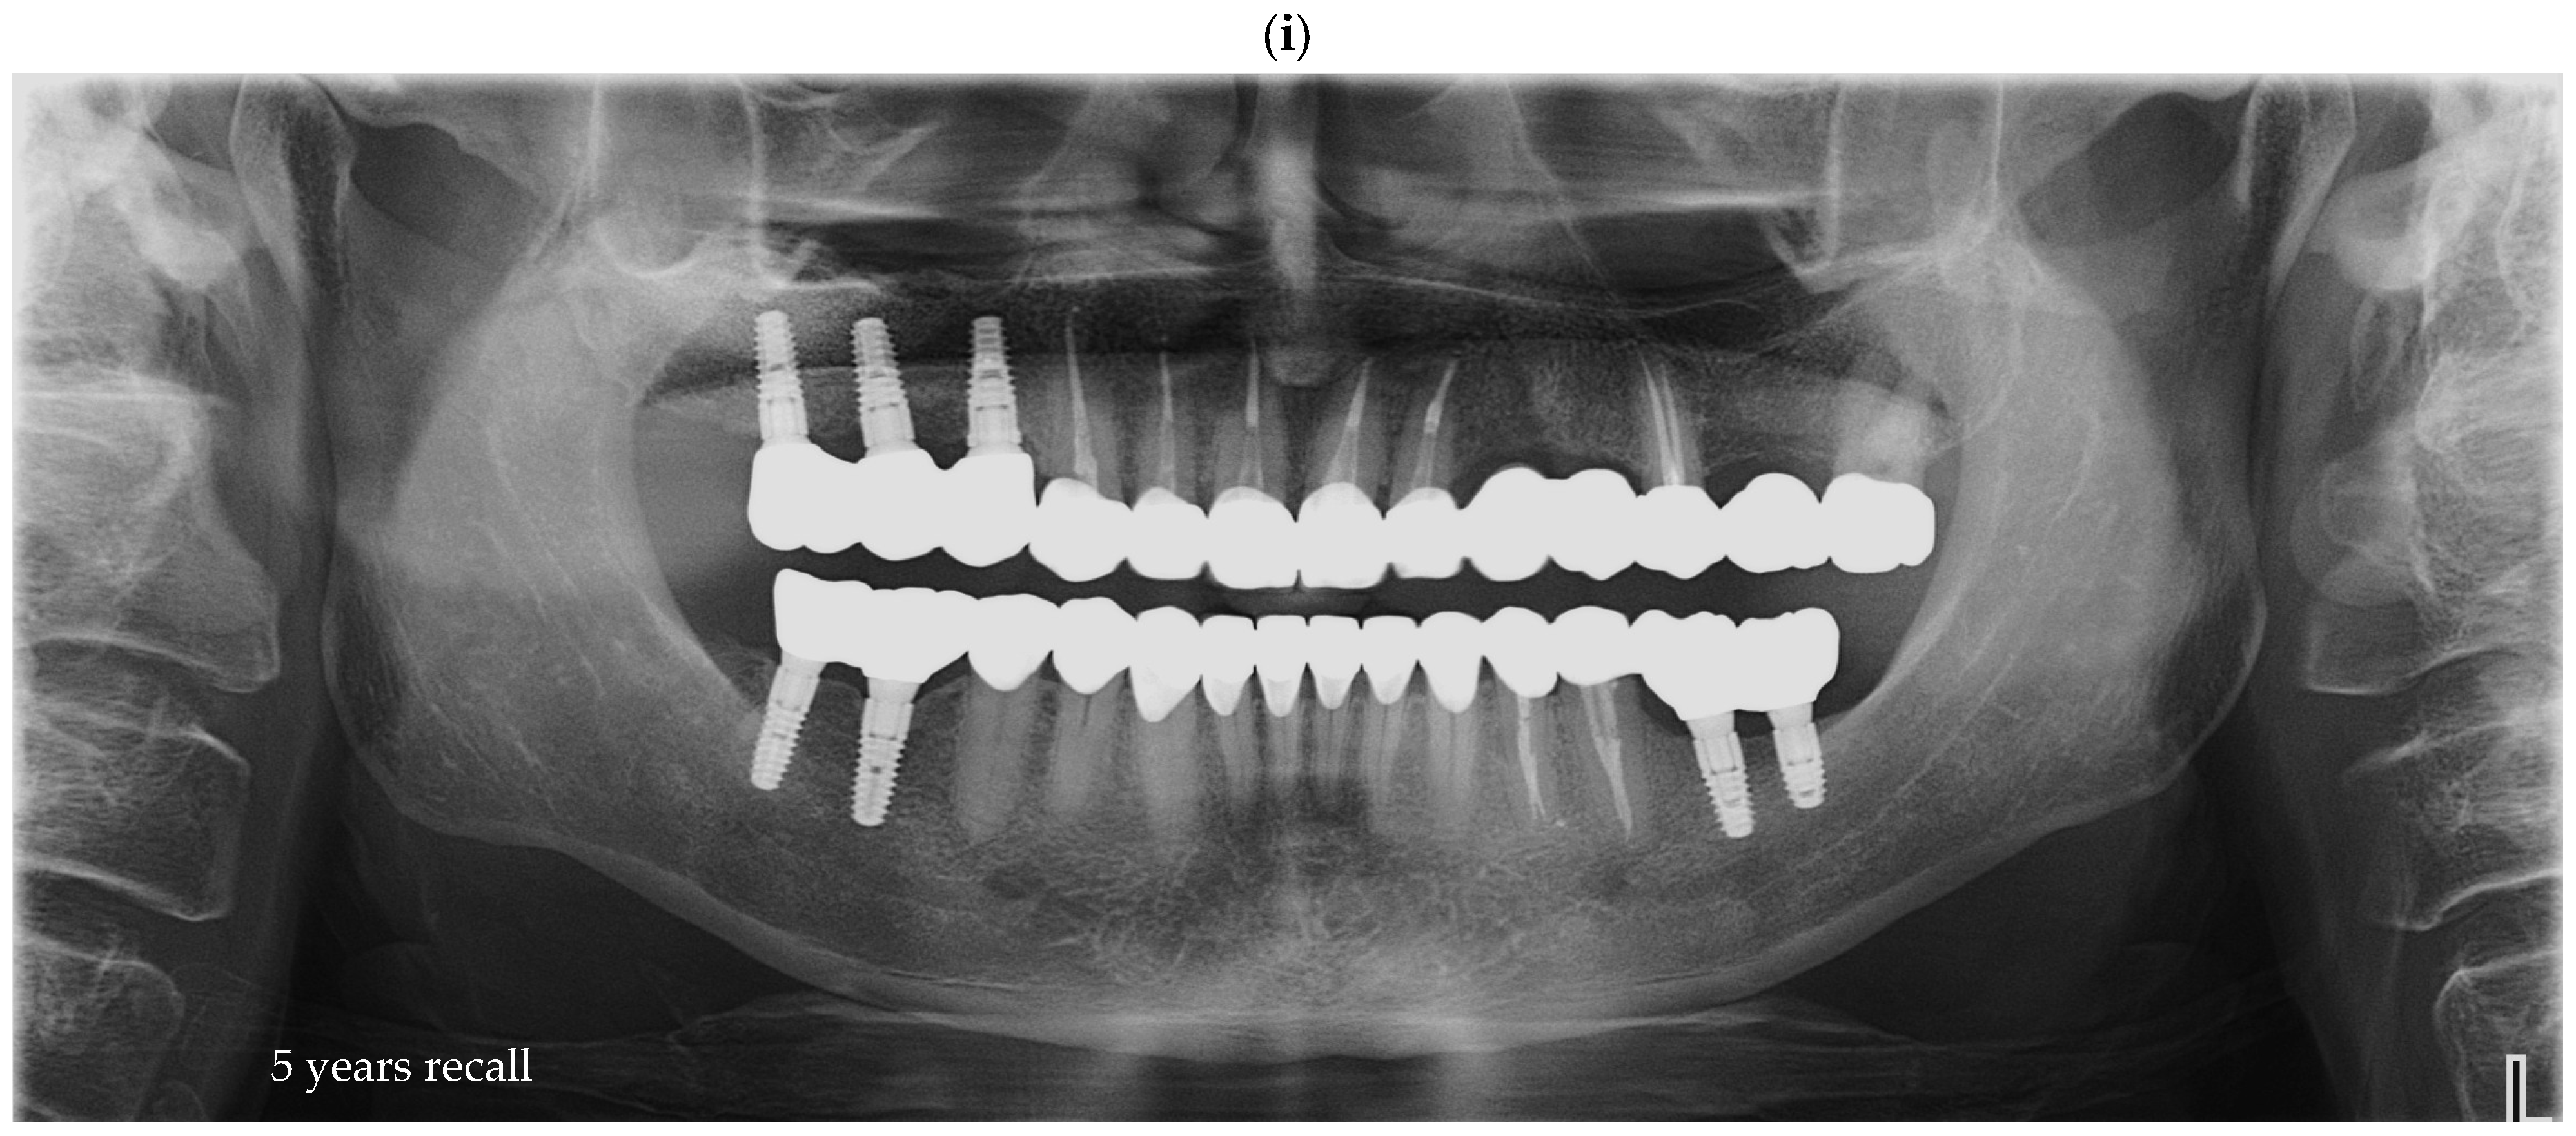

Radiographic assessments were conducted during the initial impression phase, provisional restoration try-in, and final prosthesis delivery. CBCT, panoramic radiographs, and intraoral periapical radiographs were used to visualize the implant–abutment interface and prosthetic fit. All imaging was performed using standardized exposure parameters, with radiographs analyzed using calibrated digital imaging software to assess marginal gaps and seating accuracy. In Figure 6, a representative case is presented, illustrating the radiographic sequence from the patient’s initial visit to the annual follow-up appointments. Figure 6a shows the panoramic radiograph (OPG) obtained at the first visit. Figure 6b corresponds to the postoperative image taken immediately after implant placement. Figure 6c illustrates the situation six months after surgery, following the delivery of the temporary restoration. Figure 6d shows the radiograph taken six months after provisional restoration was delivered, immediately after delivery of the definitive restorations. Figure 6e–i represent the annual recall examinations. Vertical marginal discrepancies were quantified as linear distances in millimeters (mm) at the implant–abutment interface. All radiographic examinations (periapical, panoramic, or CBCT) included in the analysis were obtained strictly for clinical diagnostic and follow-up purposes according to standard treatment protocols. No supplementary exposures were performed for research reasons. Data were analyzed retrospectively from existing clinical records. Impression procedure duration was recorded in minutes (min). Patient-reported outcomes were collected as Visual Analog Scale (VAS) scores on a 1–10 scale (dimensionless) (Appendix A). The same diagnostic criteria were applied across both digital and conventional groups to ensure consistency.

Figure 6. Representative panoramic radiographs obtained at different clinical stages of treatment. All radiographs were part of standard patient follow-up and were retrospectively analyzed; no additional exposures were performed for research purposes. (a) initial panoramic radiograph at the first visit; (b) postoperative image following implant placement; (c) six-month follow-up after surgery, at delivery of the temporary restoration; (d) radiograph taken six months after temporary restoration, immediately after delivery of the definitive restorations; (ei) annual recall examinations demonstrating stable peri-implant bone levels over time.